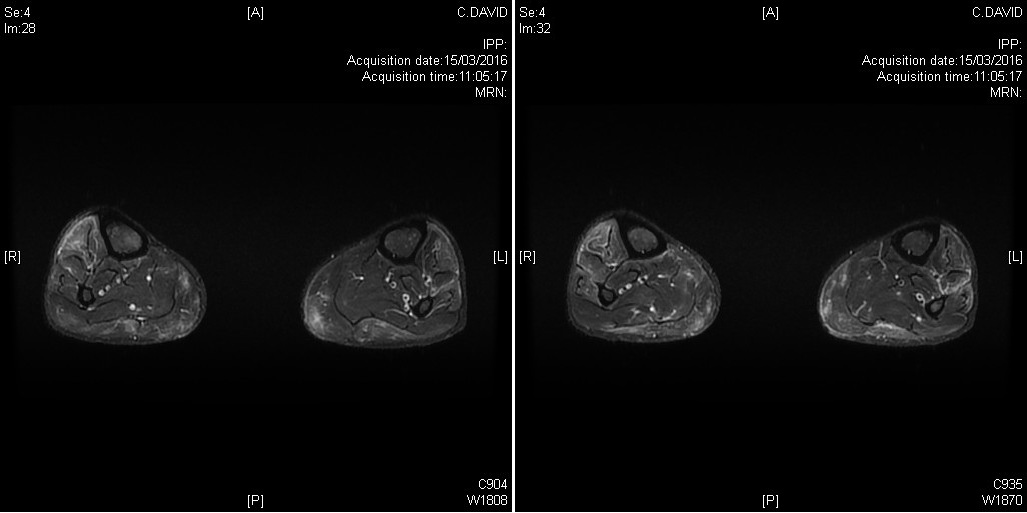

Tableau clinique de polymyosite avec atteinte clinique et IRM des deux jambes